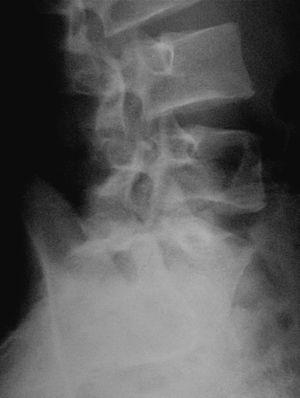

En la visita següent el pacient es presenta amb radiografies que confirmen el diagnòstic d'espondilòlisi L5 unilateral dreta (figs. 1 i 2). D'acord amb el document de consens de la Societat Catalana de Medicina de l'Esport, se sol·licita una gammagrafia òssia planar (GOP) amb tomografia computaritzada per emissió de fotó simple (SPECT). Es decideix continuar amb el mateix tractament i s'assabenta el pacient que serà un tractament a llarg termini.

Figura 2